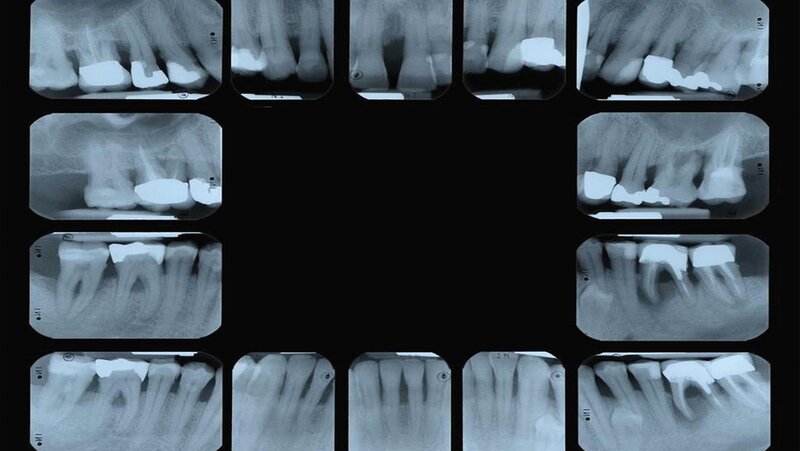

Da der histologische Nachweis einer erfolgreichen Furkationsregeneration kein praktikabler Endpunkt für kontrollierte klinische Studien ist, dienen Veränderungen bei direkten Knochenmessungen (offene Messungen: horizontales Knochensondierungsniveau bei der Operation und während eines „Re-entry“-Eingriffs) als primäre Ergebnisvariablen zur Bewertung des klinischen Erfolgs, während geschlossene Messungen wie der klinische Attachmentgewinn (horizontales/vertikales Attachmentniveau (CAL)), die Reduktion der Taschensondierungstiefe (TST) und röntgenologische Beurteilungen als sekundäre Zielparameter dienen können [Machtei, 1997]. Zu den von den Patienten berichteten Ergebnissen nach einer regenerativen Furkationschirurgie können postoperative Schmerzen, die Komplikationsrate, der wahrgenommene Nutzen und die Veränderung der Lebensqualität gehören.